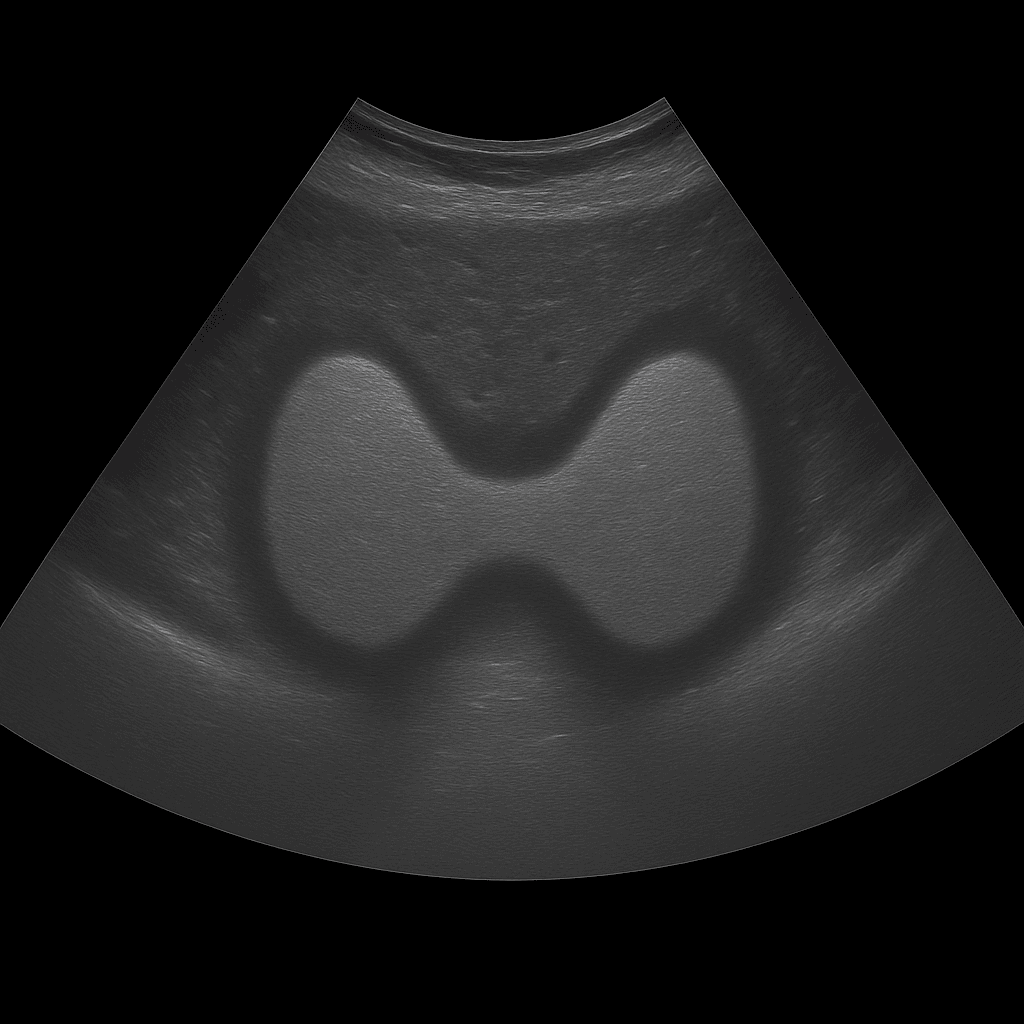

A thyroid ultrasound is used to assess the size, shape, tissue structure and any lumps or cysts of the gland. The examination is performed by a specialist in radiology and provides detailed real-time images of both lobes of the thyroid gland and the surrounding tissues in the neck. Thyroid ultrasound is used as the first-line method for investigating lumps, swelling, an enlarged thyroid gland or abnormal thyroid tests.

Unlike MRI and CT, which are rarely used for the soft tissues of the thyroid gland, ultrasound provides a high-resolution and direct image of the tissue. Ultrasound can also distinguish between solid and fluid-filled lesions and is often used to guide fine-needle aspiration (puncture) of suspicious nodules. It is a rapid, radiation-free method that provides an immediate visual basis for diagnosis.

The examination is performed while you lie on your back with your head slightly tilted back to expose the neck area. A gel is applied to the skin and the doctor moves the ultrasound probe over the thyroid gland. Both lobes and the isthmus (the connection between the lobes) are carefully assessed in longitudinal and cross-sectional views. If necessary, nearby lymph nodes in the neck can also be examined.